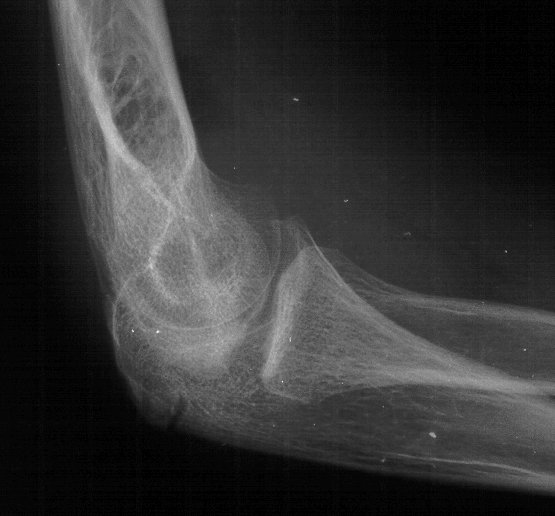

Plain films show humeral osteophytes and posttraumatic changes of the capitellum and radial head.

Click for larger image